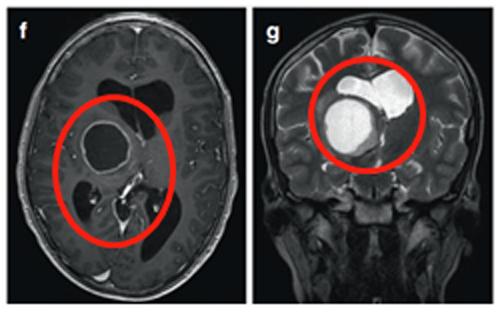

6岁男童临床表现为头痛、间歇性左上肢震颤。MRI(FLAIR序列)显示双侧丘脑肿瘤,右侧大于左侧,累及尾状核头部。脑室轻度增大,伴膈膜水肿和肿瘤内部囊肿。

治疗团队先行左额部内窥镜活检和鼻中隔造瘘术,后续行左枕脑室-腹腔分流术。组织病理诊断为WHO III级间变性星形细胞瘤,H3K27M、p53、BRAF V600E突变免疫阴性,MIB-1增殖指数达40%。

制定综合治疗方案:同步替莫唑胺(TMZ)和放射治疗(59.4Gy),后续完成12周期替莫唑胺治疗(累计剂量200mg/m²)。确诊后15个月影像学表现稳定,临床症状缓解,生活质量显著提升。